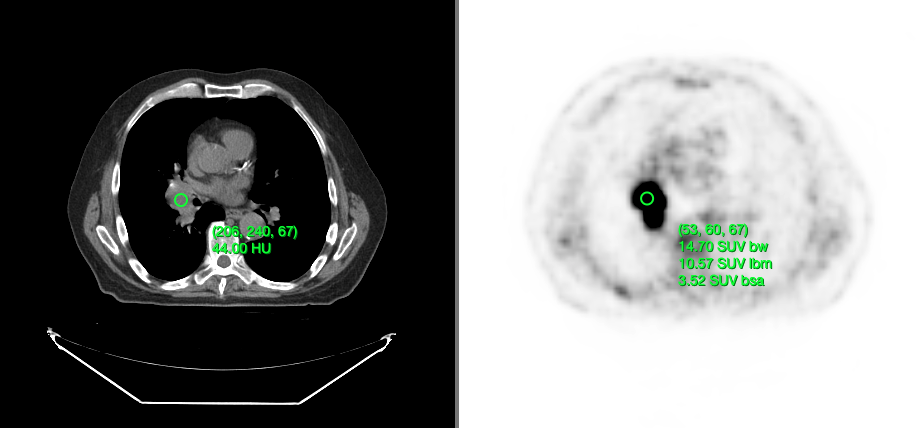

Below, you can see a screenshot of the annotation tools that are available in Cornerstone3DTools.

Dynamic tool statistics

Cornerstone3DTools is capable of calculating dynamic statistics based on the modality of the volume being rendered. For instance, for CT volumes a ProbeTool will give Hounsfield Units and for PET it will calculate SUV stats.